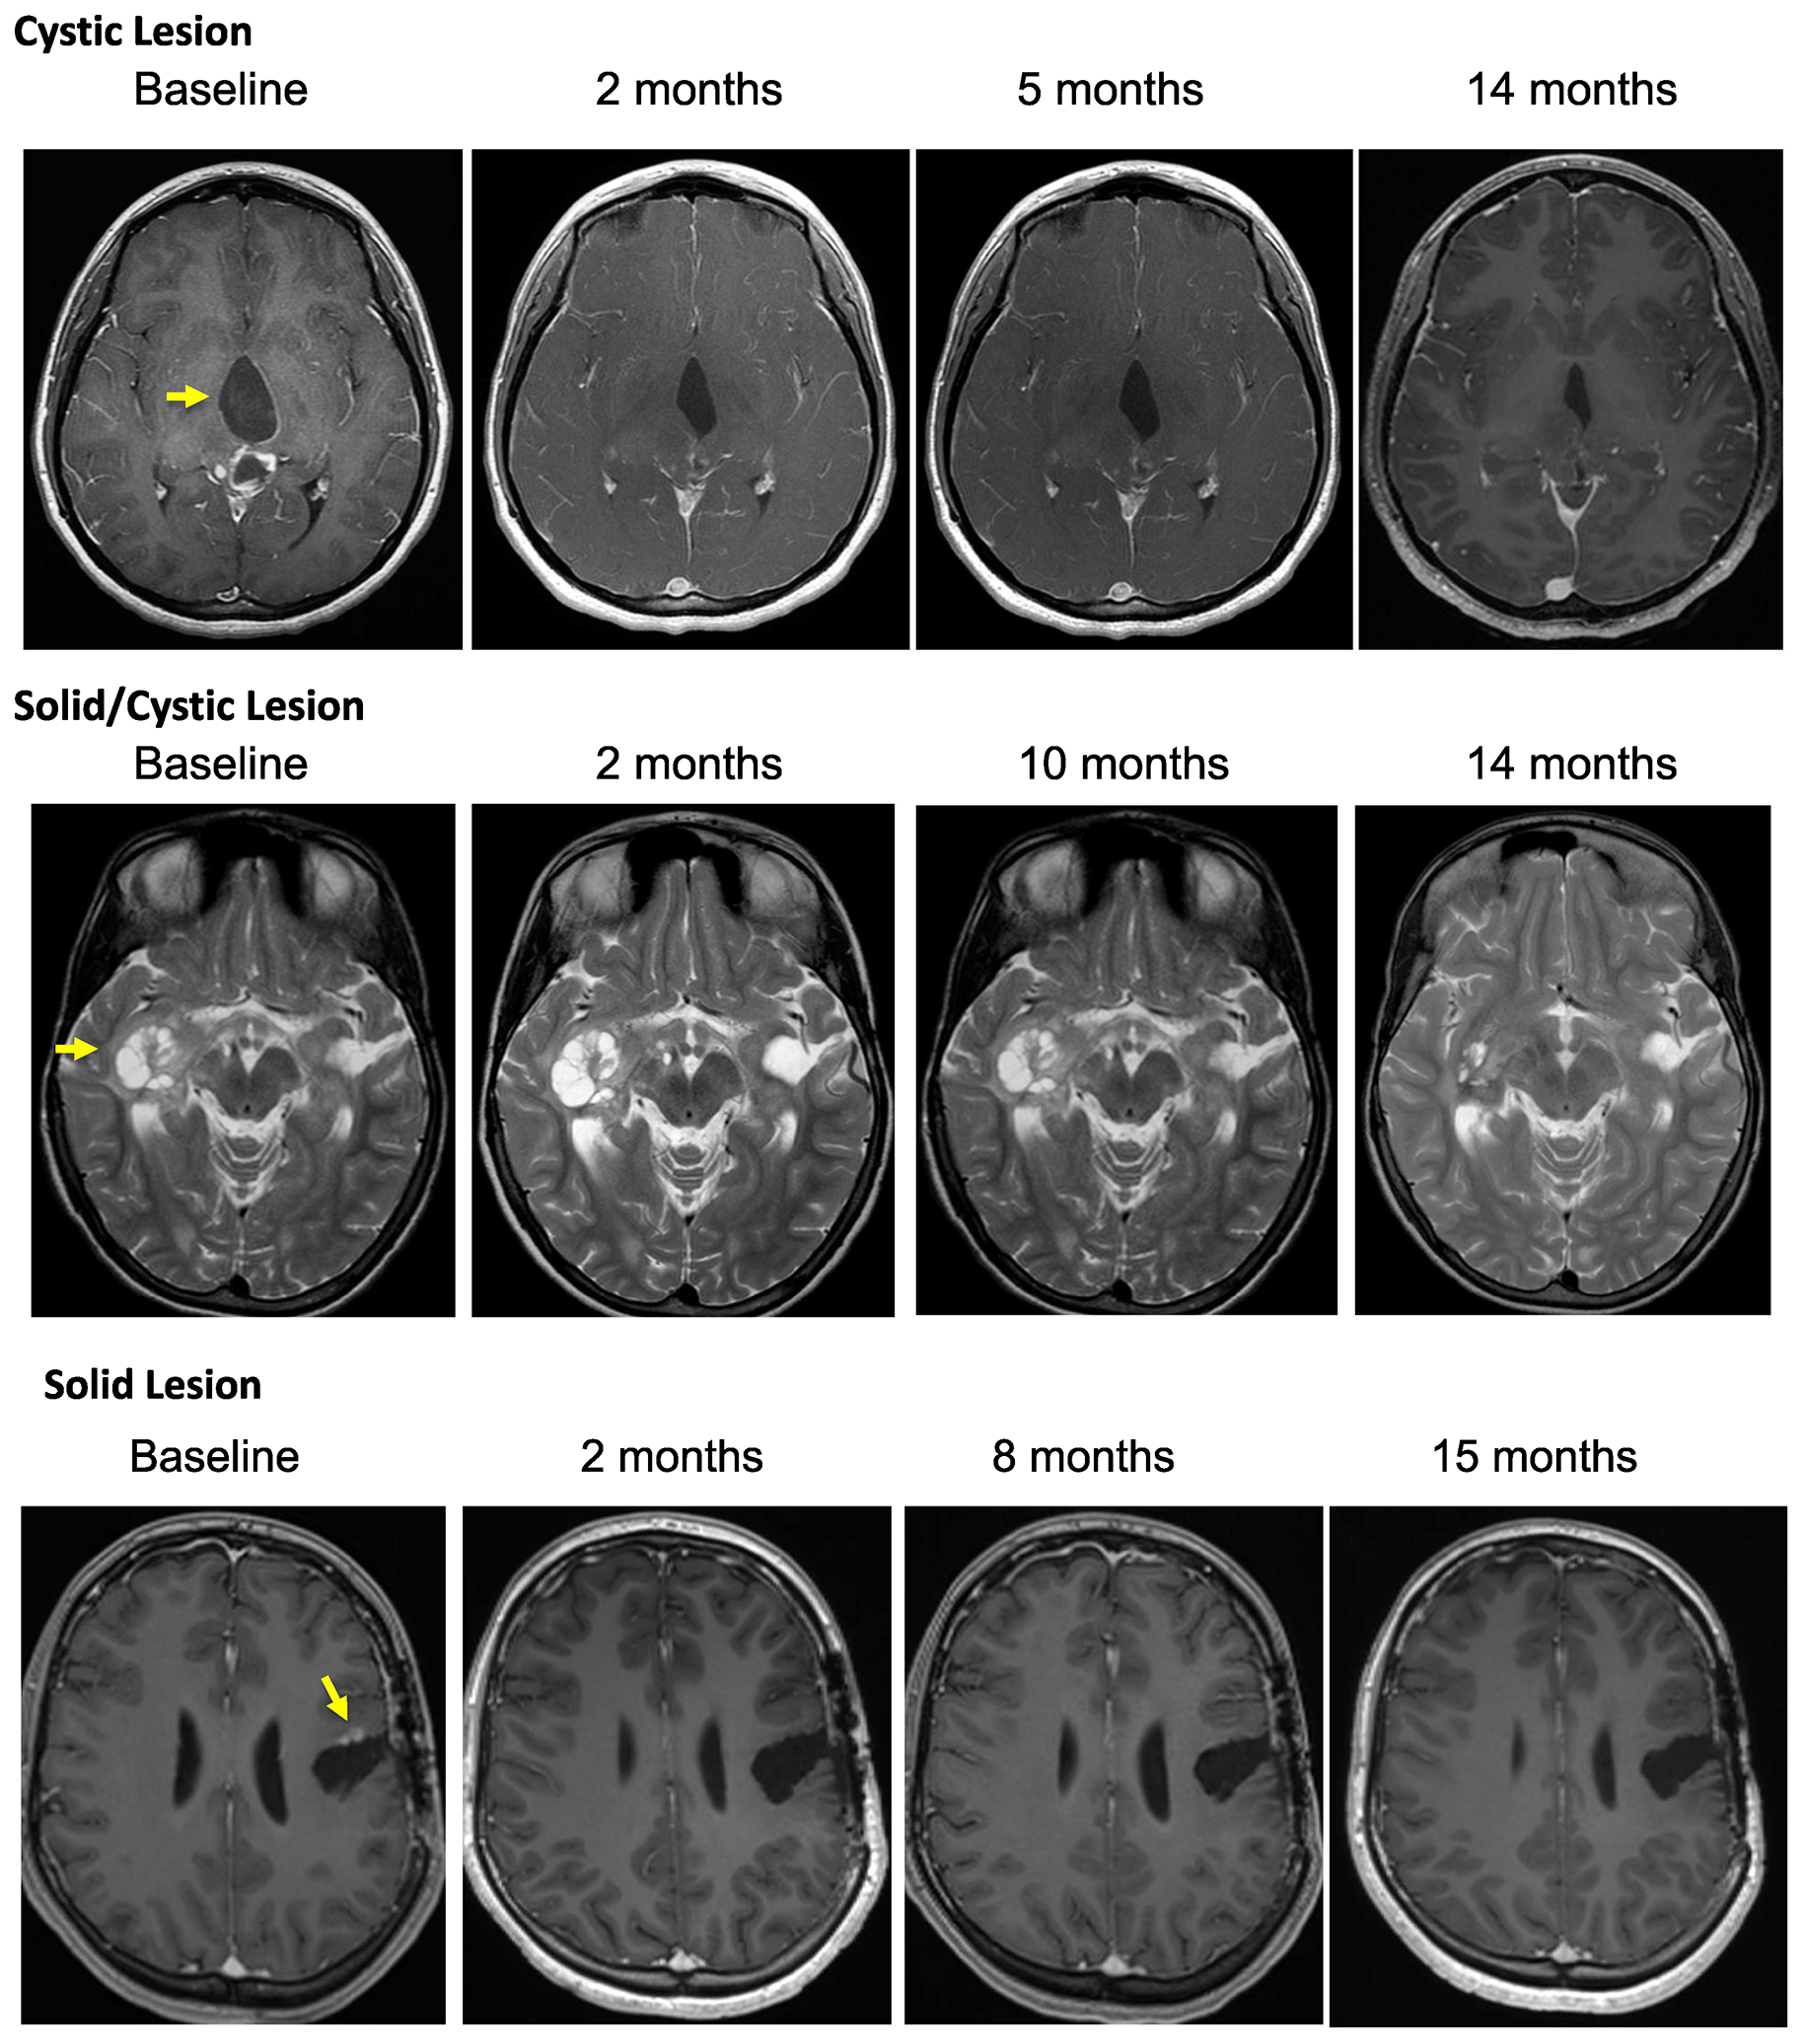

Patient outcomes are reported for the 19 patients treated. The median number of vemurafenib courses was 23 (range 3 to 63). Centrally reviewed best radiographic responses included 1 CR, 5 PR, and 13 patients with SD (Figure 1). Solid tumor component was measured for determination of outcomes in 10 patients, with the remaining 9 patients with no measurable solid component undergoing measurement of solid/cystic lesion for outcome determination. Figure 1 demonstrates best response percent decrease in tumor size during the course of treatment with vemurafenib. As shown in Table 3, responses were durable with some patients having continuous response for over 40 months. Cystic lesions appeared to decrease more in size compared to the solid lesions with vemurafenib therapy (Table 4). Interestingly, we found that 10 of the patients in our cohort who presented with contrast-enhancing tumors were found to develop loss of enhancement during treatment. Examples of radiographic responses are shown in Figure 2, with representative solid, cystic, and mixed solid/cystic lesions.

Figure 2: Depicted are representative images of subjects treated on PNOC-002 demonstrating. (A) regression of a contrast enhancing cystic lesion on a contrast, T1 weighted MR image over time; (B) regression of a solid/cystic lesion on a T2 weighted MR image over time; (C) regression of a contrast enhancing solid lesion on a contrast, T1 weighted MR image over time.